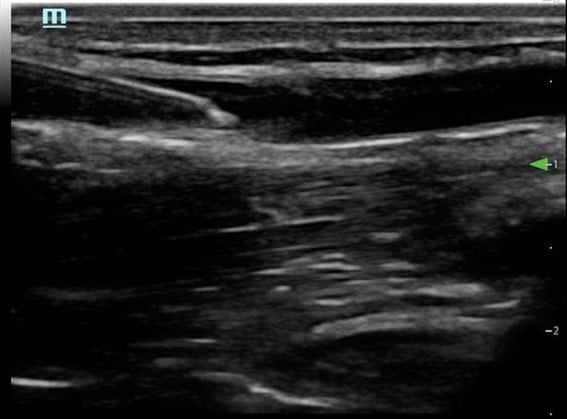

- Follow the needle tip until it enters the vein. (Fig. 4)The needle tip is followed into the lumen of the vessel. It is essential that the transducer is advanced before the needle tip so as not to mistake the needle shaft for the tip and risk potential damage to the posterior wall of the vessel. Advance the needle tip in conjunction with the transducer for 1-2 cm additionally to ensure enough of the catheter is in the vessel.3 (Fig. 5)

Figure 5. Short axis approach: Needle tip entering vessel